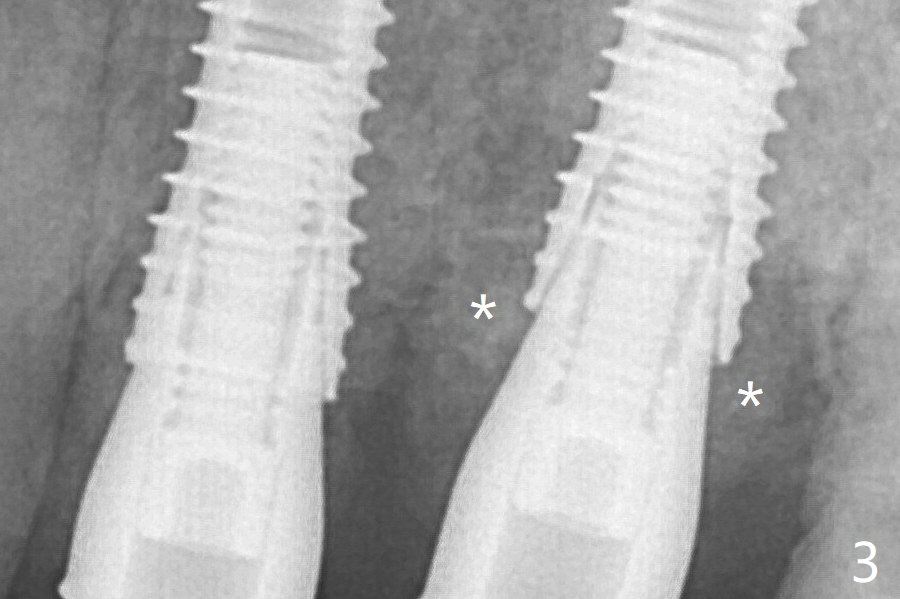

After correction of trajectory at #12 and 3 mm drill for 16 mm at the sites, two of 3.8x16 mm implant are placed with insertion torques of 35 and 15 Ncm, respectively (Fig.2).  Before and after change into shorter abutments (4.5x4(4) and (5)), Vera Graft is placed (Fig.3 *).  The allograft appears to have been incorporated into the host bone nearly 4 months postop (Fig.5).